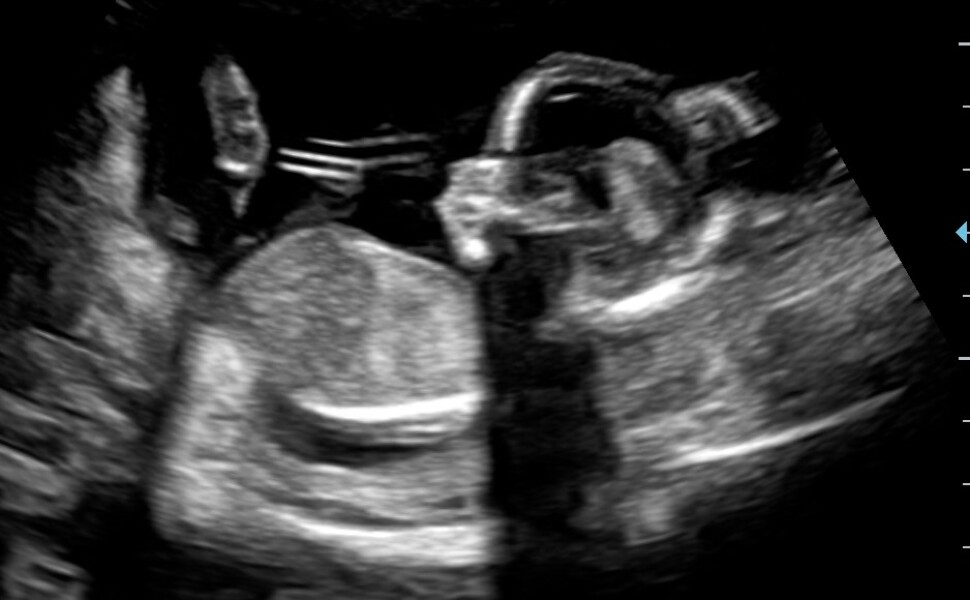

I'm currently 16w1d following IVF and a previous MMC at 8w in January. I suffered with a lot of cramping my entire first trimester and a fairly significant bleed about 5w2d but yesterday (and I can't believe I can say this) we found out we're having a son!!! I'm going to be a boy mum I'm so excited and we got to see him again wiggling around after so much anxiety in the run up.

@Lollypop25 that is brilliant news, I’m so happy for you! And such a lovely scan pic too šŸ˜ŠšŸ’œ